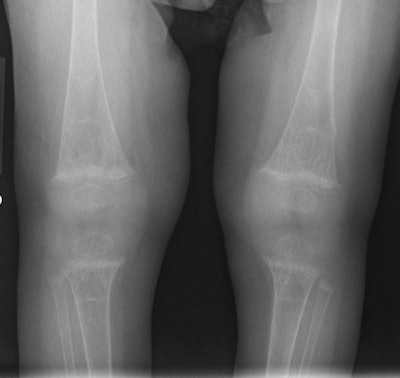

![]() |

| Fracture in rachitic bone. Anteroposterior radiograph of the bilateral knees in a patient with severe rickets demonstrates diffuse osteopenia and subtle cortical irregularity at the distal left femur, consistent with a nondisplaced transverse fracture. |